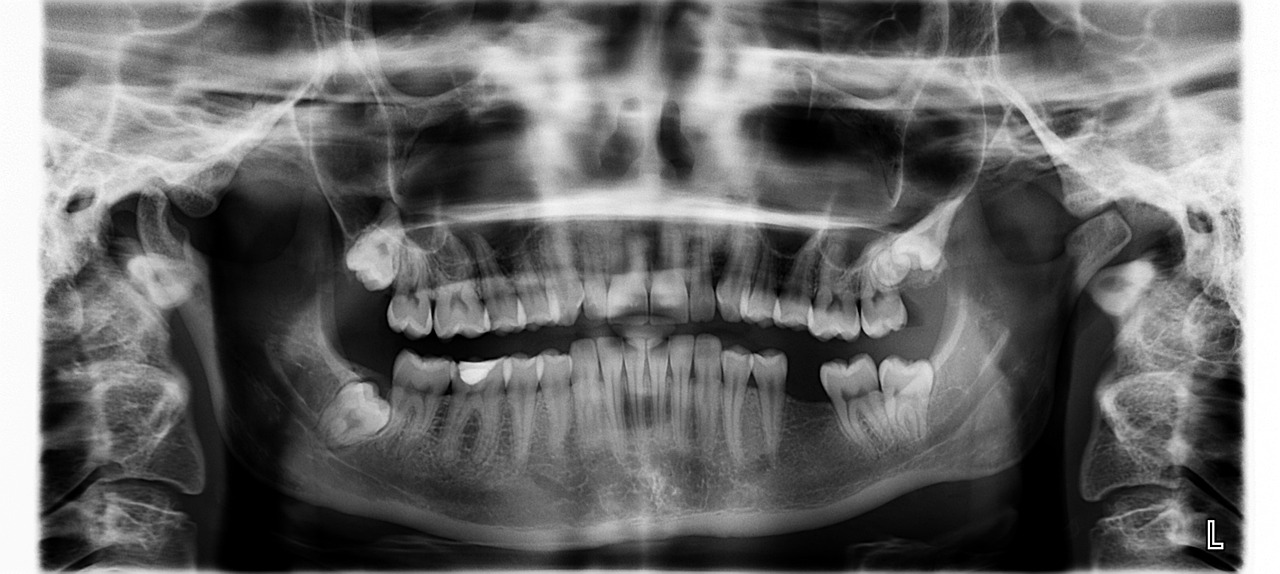

📷 사진 펼쳐보기 / 접기